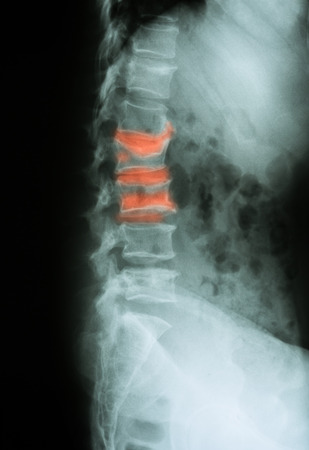

Cirugía curativa. En las ocasiones en el que el tumor primario tiene buen pronóstico y es posible quitar la metástasis por completo hay que realizar una cirugía que elimine la metástasis por completo. Se trata de cirugías muy complejas, agresivas que normalmente incluyen la retirada de una o varias vértebras al completo, siendo necesario aportar tornillos y cajas intersomáticas para recuperar la estabilidad espinal.

Estabilidad Espinal. Mantener la estabilidad espinal es primordial, como ya os hemos contado la metástasis vertebral al crecer puede destruir la vértebra generar dolor y provocar una fractura, deformidades o incluso complicaciones neurológicas. En los casos de metástasis potencialmente inestables pueden usarse corsé o realizar técnicas menos agresivas como la vertebroplastia, en los casos de metástasis inestables es necesario realizar fijaciones vertebrales.